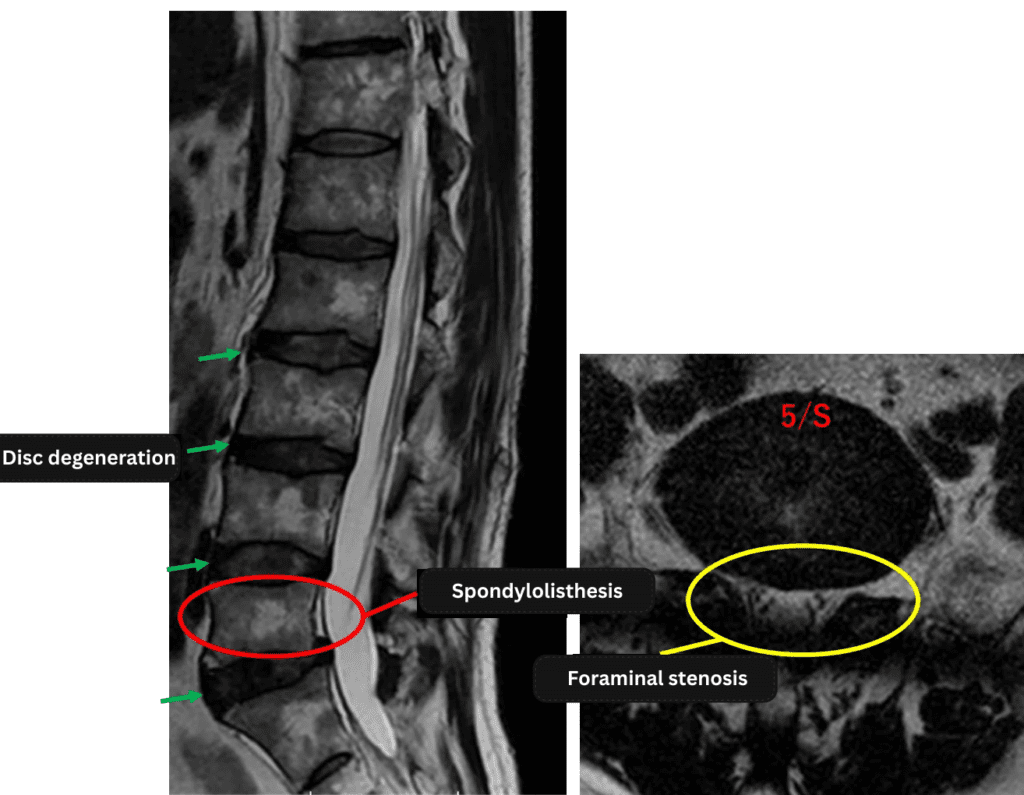

Imaging and findings

L1/2: Normal

L2/3: Normal

L3/4: Mild intervertebral disc degeneration

L4/5: Disc bulging

L5/S1: Disc degeneration, disc bulging, spondylolisthesis

The above findings were also observed on the imaging.

Intervertebral disc degeneration and spondylolisthesis were observed and are considered highly likely contributors to the patient’s primary symptoms.